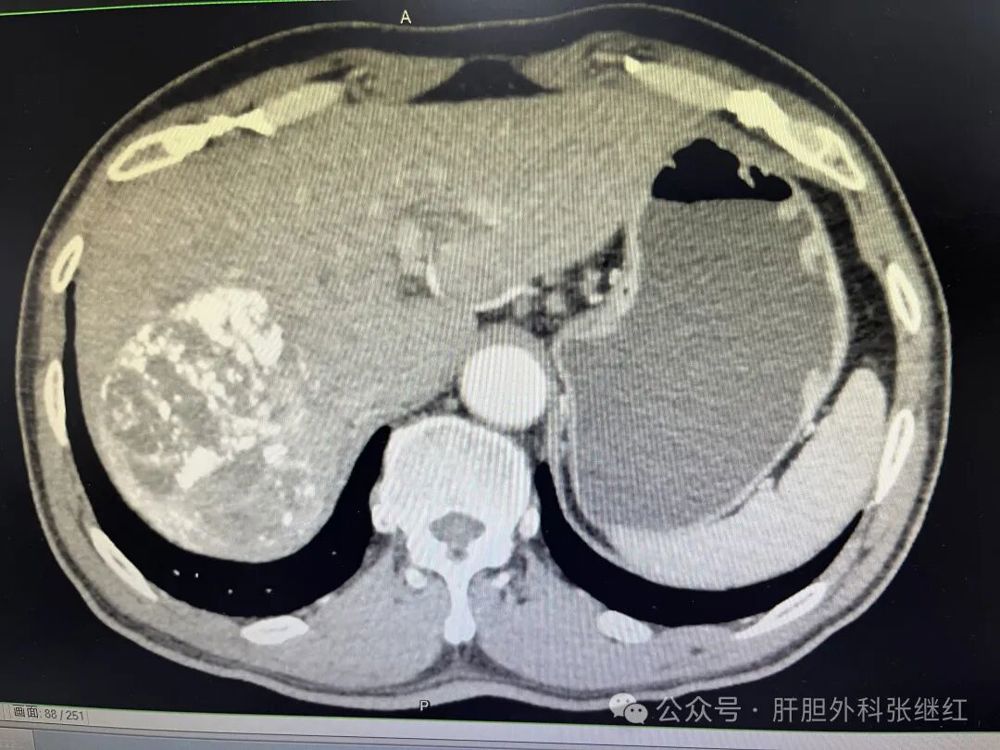

男性62岁病人,入院时肿瘤位于右肝,瘤体巨大长径约10.2厘米,且伴有门静脉右支癌栓形成,多学科会诊建议先行新辅助治疗后手术。征求病人及家属意见后采取双安方案行靶向免疫治疗3个疗程(约2个月),肿瘤略缩小,长径约8.2厘米,但未达到PR标准,停靶向免疫治疗四周,拟行腹腔镜右半肝切除术。由于病人经济状况不佳,坚决要求开腹手术,于是经术前评估和术前讨论行右半肝切除术。经右肋缘下切口进腹,探查肝脏呈轻度肝硬化,肿瘤占据右肝中心部位,未见肝内转移灶,肝脏周围少许炎性粘连,未发现肝外转移灶,为避免术中挤压肝组织引起肿瘤经血管转移和肿瘤破裂,决定行前入路右半肝切除术(又称原位右半肝切除术)。常规切除胆囊,鞘外分离右肝蒂,结扎右肝蒂后见缺血线明显,依缺血线画切肝线,以15+5min模式间歇性阻断肝门,原位离断肝实质,进入肝实质后以肝中静脉为导向离断肝实质直至下腔静脉前壁,切割闭合器离断右肝蒂,结扎切断从右肝进入下腔静脉的肝短静脉,切割闭合器离断右肝静脉,离断右肝周围韧带,至此右半肝已完整切除。取除标本,肝断面置橡胶引流管,关闭切口,术毕。术中发现该病例比未经靶向免疫治疗的病例更容易渗血,但手术顺利,术后病人恢复良好。

f9aca9c344c7450a92e24c7a410a7d1f.jpg

入院时CT